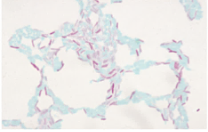

- Mycobacterium属は細胞壁に多量の脂肪酸 ( ミコール酸 ) を含み , 一度染色されると酸やアルコールで脱色されにくい性質を有する ( 抗酸性 ) → この性質を利用し , 脱色に塩酸アルコールを使用して抗酸菌のみを染色するZiehl-Neelsen染色がある

- 細胞壁の豊富な脂肪酸によりグラム染色では染色されず , 菌体がガラスの傷のように見える